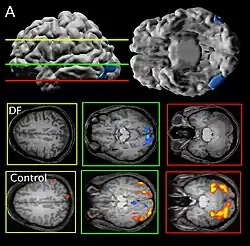

Her agnosia is thought to be caused by a bilateral lesion to her lateral occipital cortex, an area thought by dual-stream proponents to be the ventral "object recognition" stream.[1]

Patient DF's brain damage resulted from hypoxia due to accidental carbon monoxide poisoning in 1988, when she was 34 years old.[2] The lateral occipital cortex (LOC) in her brain is severely damaged and shows no activation presented with line drawings of common objects where healthy people usually do. Moreover, there is a reduction of white matter connections between LOC and other areas.[3] There is also some shrinkage in the intraparietal sulcus, often implicated in the dorsal stream for visuomotor control. The fusiform face area is intact. This would suggest the problem in DF's perception is disconnectivity between higher and lower order functioning.[4]

Recent MRIs have shown many enlarged sulci, like the intraparietal sulcus, parieto-occipital sulcus, and left calcarine sulcus, indicating atrophy.[4] Her visual field remains intact up to 30 degrees.[1]